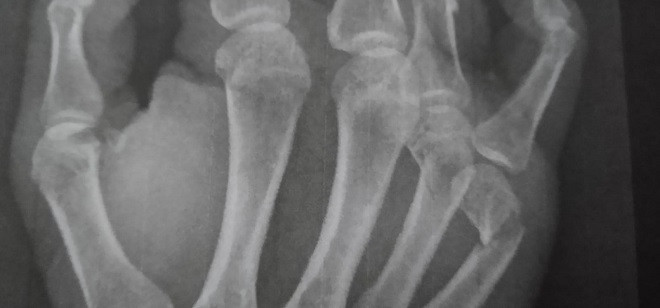

Radiografía de la mano derecha del funcionario que ha resultado herido.

Como consecuencia tuvo que ser atendido en la enfermería del centro penitenciario y posteriormente tras las radiografías que le practican en el servicio de urgencias del Hospital se le diagnostica la fractura de dos huesos de la mano.